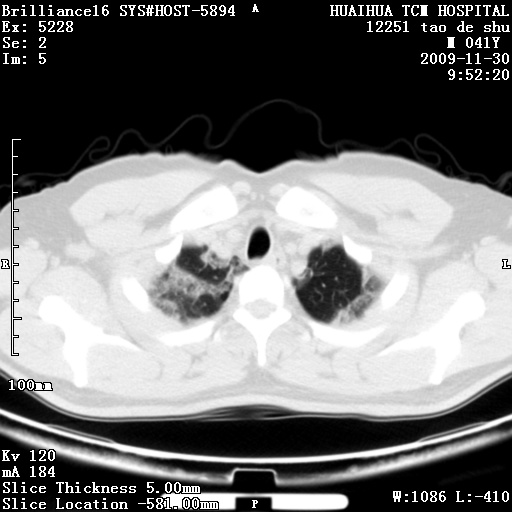

男性,41岁,林业局干部。5天前(2009-11-25)因受寒咳嗽发热在市一医院门诊就诊,胸片报告支管炎。门诊治疗无好转,遂转入我院住院治疗。现主要为发热,38度,咳嗽较轻。血象不高,中性72%,嗜酸性细胞未见报告。血小板8万。尿有蛋白管型。肝功能异常。心电图:阵发性心动过速。请分析ct是什么病。

补充图片:

两肺外带斑片状及磨玻璃样高密度灶,考虑感染性病变,过敏性肺炎不除外。

考虑非肺染 肝脏多发性小囊肿

考虑间质性肺炎。肝脏多发性小囊肿